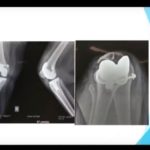

Proximal humerus fractures – Fix or replace?

Courtesy: Saqib Rehman, Temple University, Philadelphia, USA